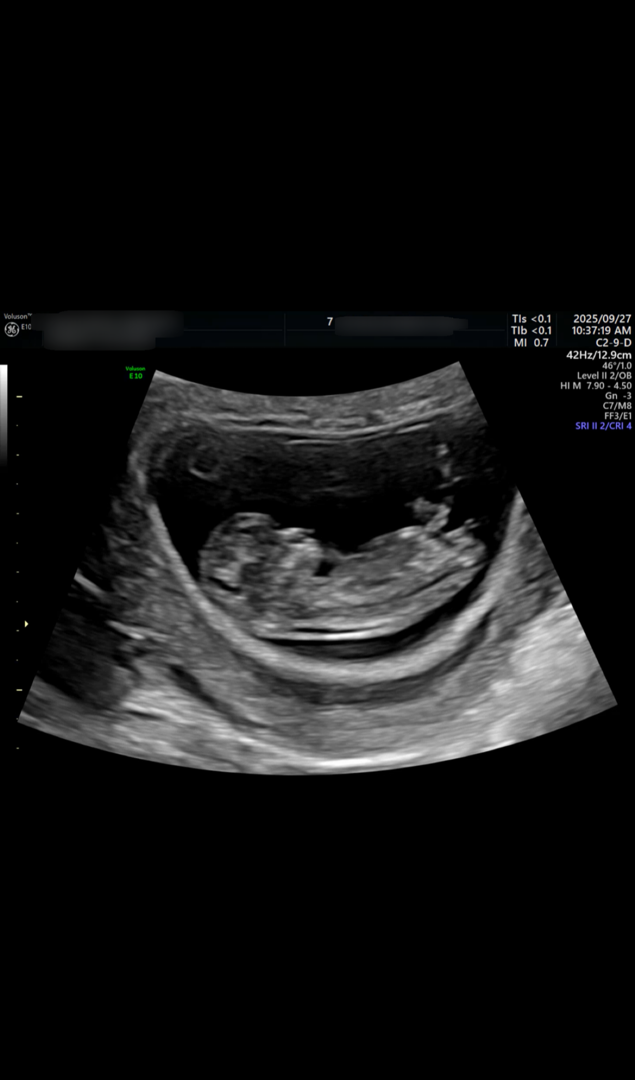

11주 4일차 초음파 각도법 봐주실수있나요?

11주 4일차때 초음파 사진인데 아들?딸? 어떤 성별로 보이시나요?? (12주 0일차에 병원갔을때는 아직 성별을 알수없다 하셨고 연휴가 껴서 니프티 검사 결과는 한참 뒤에 나온다네요ㅠ)